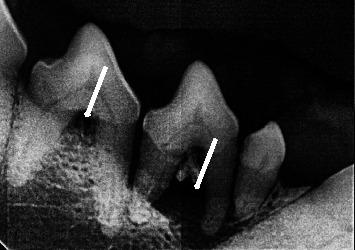

With the objective to evaluate the prevalence of periodontal disease (PD) and monitor the most affected teeth in dogs under the subtropical conditions in Mexico, 184 randomly selected dogs underwent a periodontal examination. Of the evaluated dogs, 78.8% showed some degree of gingivitis most of them (76.6%) with a moderate index, and 30.4% presented some degree of PD being most of them of a mild degree. Old age and small size dogs were more prone to develop PD as reported elsewhere. Higher mobility index and furcation were seen in maxillary teeth 108 and 208 and mandibular teeth 308 and 408, but some other teeth were involved in less proportion. On probing, bleeding was observed in maxillary teeth 202, 11, 102, and 202 and mandibular teeth 309 and 409. Dental plaque and calculus were more frequent in maxillary teeth 202 and 102 and mandibular teeth 309, 310, and 409. Finally, dental loss was observed with more frequency in all maxillary incisors (102, 201, and 202) and molars 109 and 209; mandibular molars 411 and 311 were more prompt to be losed. This study demonstrates the high prevalence of gingivitis and development of PD in dogs in subtropics in Mexico and reveals the predisposition of some maxillary and mandibular teeth to develop PD and consequently their loss. The clinical implications of the study indicate that special attention should be paid to these teeth to be checked when the dogs come for consultation, during brushing and in dental prophylaxis.

为评估墨西哥亚热带条件下犬牙周病(PD)的患病率并监测受影响最严重的牙齿,对184只随机挑选的犬进行了牙周检查。在接受评估的犬中,78.8%表现出一定程度的牙龈炎,其中大多数(76.6%)指数为中度,30.4%表现出一定程度的PD,其中大多数为轻度。如其他地方所报道,老年犬和小型犬更容易患PD。在上颌108和208牙齿以及下颌308和408牙齿中观察到更高的松动指数和根分叉,但其他一些牙齿受累比例较低。探诊时,在上颌202、11、102和202牙齿以及下颌309和409牙齿中观察到出血。牙菌斑和牙结石在上颌202和102牙齿以及下颌3(此处原文有误,应为309)、310和409牙齿中更为常见。最后,在上颌所有切牙(102、201和202)以及磨牙109和209中观察到牙齿脱落的频率更高;下颌磨牙411和311更容易脱落。本研究表明墨西哥亚热带地区犬牙龈炎的高患病率和PD的发生,并揭示了一些上颌和下颌牙齿患PD并因此脱落的易感性。该研究的临床意义表明,当犬前来咨询、刷牙和进行牙齿预防时,应特别注意检查这些牙齿。